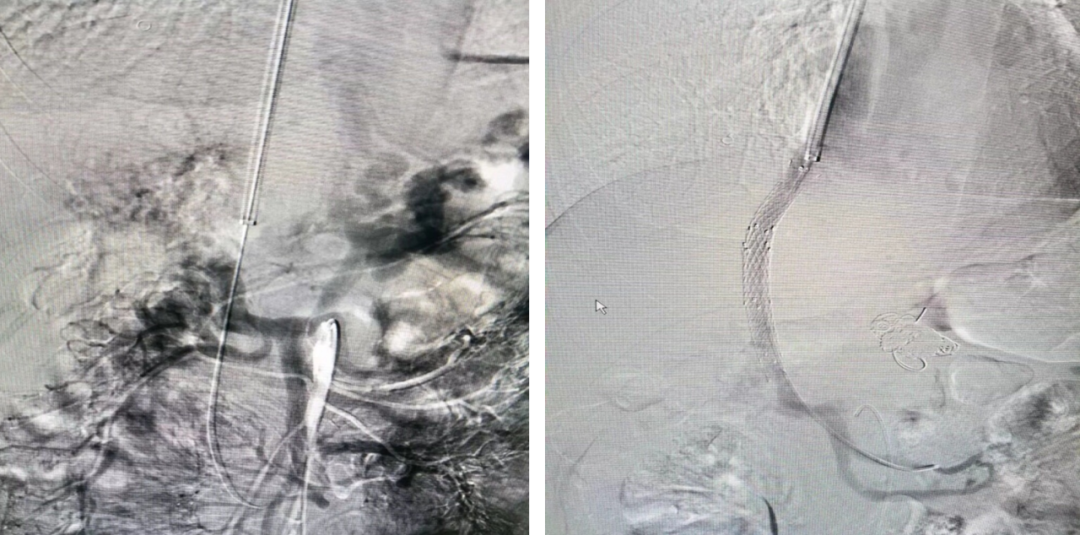

门静脉血栓(PVT)

联合使用 AngioJet、Straub 吸栓系统 经 TIPS 入路清除肠系膜上静脉血栓;

近年采用 Indigo 抽吸导管 成功处理肝移植术后门静脉血栓。

肝硬化门静脉血栓—TIPS联合AngoJet

肝硬化门静脉血栓—TIPS联合Straub吸栓

近期尝试Indigo抽吸导管用于肝移植术后门静脉血栓